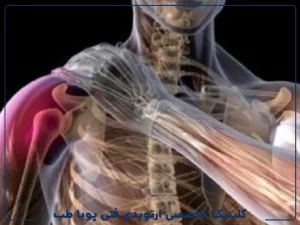

آسیب شانه ناشی از ورزش آسیبهای شانه یکی از شایعترین مشکلات حرکتی در ورزشکاران هستند، بهخصوص در رشتههایی که حرکات بالای سر، پرتابها، یا فشار